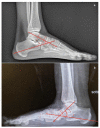

Adult acquired flatfoot deformity (AAFD) is a disorder caused by repetitive overloading, which leads to progressive posterior tibialis tendon (PTT) insufficiency. It mainly affects middle-aged women and occurs with foot pain, malalignment, and loss of function. After clinical examination, imaging plays a key role in the diagnosis and management of this pathology. Imaging allows confirmation of the diagnosis, monitoring of the disorder, outcome assessment and complication identification. Weight-bearing radiography of the foot and ankle are gold standard for the diagnosis of AAFD. Magnetic Resonance Imaging (MRI) is not routinely needed for the diagnosis; however, it can be used to evaluate the spring ligament and the degree of PTT damage which can help to guide surgical plans and management in patients with severe deformity. Ultrasonography (US) can be considered another helpful tool to evaluate the condition of the PTT and other soft-tissue structures. Computed Tomography (CT) provides enhanced, detailed visualization of the hindfoot, and it is useful both in the evaluation of bone abnormalities and in the accurate evaluation of measurements useful for diagnosis and post-surgical follow-up. Other state-of-the-art imaging examinations, like multiplanar weight-bearing imaging, are emerging as techniques for diagnosis and preoperative planning but are not yet standardized and their scope of application is not yet well defined. The aim of this review, performed through Pubmed and Web of Science databases, was to analyze the literature relating to the role of imaging in the diagnosis and treatment of AAFD.